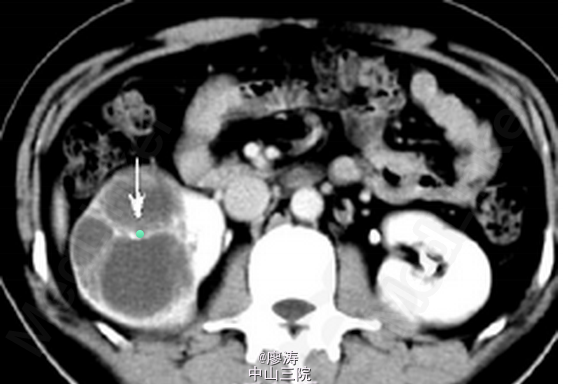

入院后查血肌酐为158umol/L,移植肾功能良好。腹部CT提示右肾巨大占位性病变,且分隔,考虑右肾肾癌。

诊断:右肾占位性病变,考虑右肾肾癌 处理:检查提示肾癌可能性大,跟患者和患者家属讨论后决定手术治疗,于是在入院后第3天在我院行右侧肾癌根治术,术后取活检确诊为肾癌,术后结合化疗。

随访:患者术后生命体征平稳,移植肾功能一直都是正常的,给予补液、预防感染、免疫抑制维持等常规术后治疗,术后2周以后恢复后出院,定期门诊规律随着。 讨论:肾移植术后由于长期服用免疫抑制剂,恶性肿瘤的发生率大大增加,其中以泌尿系统和消化系统肿瘤多见,本病例患者发生原肾肾癌,也是肾移植术后比较常见的恶性肿瘤类型,而且肾癌癌肿已经较大,暂时未发现远处转移灶,但是这个情况术后复发的可能性其实还是比较大的,要求患者增加复查的频率,有问题尽量早发现,早处理。